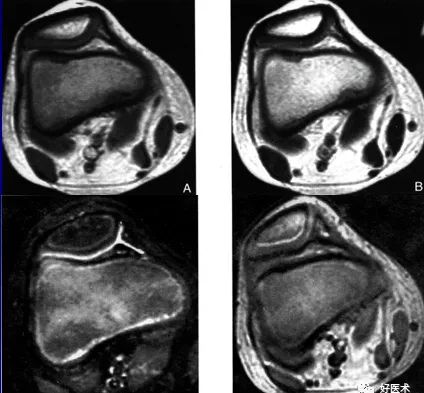

MR|判断髌骨软骨软化是以软骨内信号改变和软骨表面形态来诊断。病变可使髌骨软骨轮廓不同程度发生改变,表面毛糙,内部信号异常。

MRI表现局灶性低信号,T1T2加权像轻度轮廓改变,厚度变薄,软骨下有硬化的囊变

髌骨软骨软化症MRI表现:

Ⅱ级:

A:SE序列T1加权像

B:SE序列T2加权像

C:STIR像

D:PGE序列T1加权像